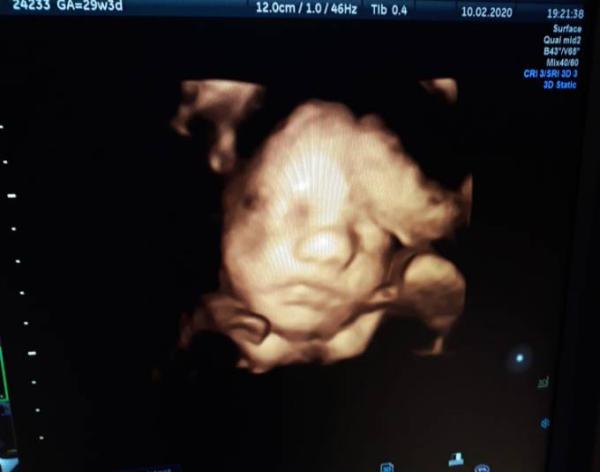

So .... nach langen 4 Wochen warten hatten wir heute Abend auch unseren Termin. Das war ein aufregender Termin ..... Blutabnahme, Rhesus Spritze, ctg und das 3. große Screening. Das Ctg war super..... alles wie es sein soll und keine wehe zu sehen. Mein Fa hat sich für das Ultraschall wie immer viel Zeit genommen .... vieles erklärt und genau geguckt. Unsere kleine Maus fühlt sich Pudel-wohl ...... hat sich mit den Kopf an die Plazenta gekuschelt, an der Hand gelutscht und mit ihrer Zunge gespielt . Wir sind total verliebt und verzaubert. Minnie wiegt 1700 Gramm und ist 40 cm groß ....der Kopfumfang beträgt 27 cm. Fruchtwassermenge und die Größe der Plazenta sowie die Durchblutung und Versorgung alles bestens. Und es ist nochmal bestätigt wurden .... es bleibt ein Mädchen. Zugenommen hab ich nicht..... Gewicht ist gleich wie vor 4 Wochen. Heute haben wir auch unser 1. 3 D Ultraschallbild bekommen ..... . Nu werd ich mich mal schnell ins Bett kuscheln .... wünsche euch einen schönen Abend und eine gute Nacht. Liebe Grüße Brina mit Minnie im Bauch

Bild zu Zurück vom Fa ♡ - Forum für April - Mamis

Das klingt nach einem tollen Termin. Und was für ein süßes Bild